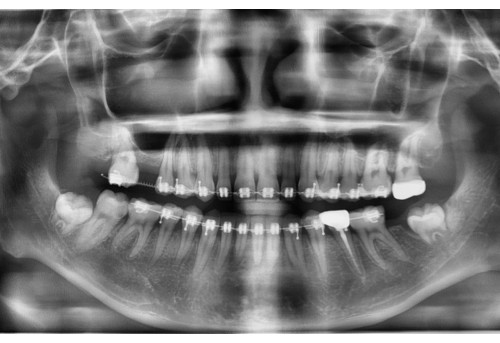

체리 증례집

• 전체

• 치아교정

• 임플란트

• 체리네이트